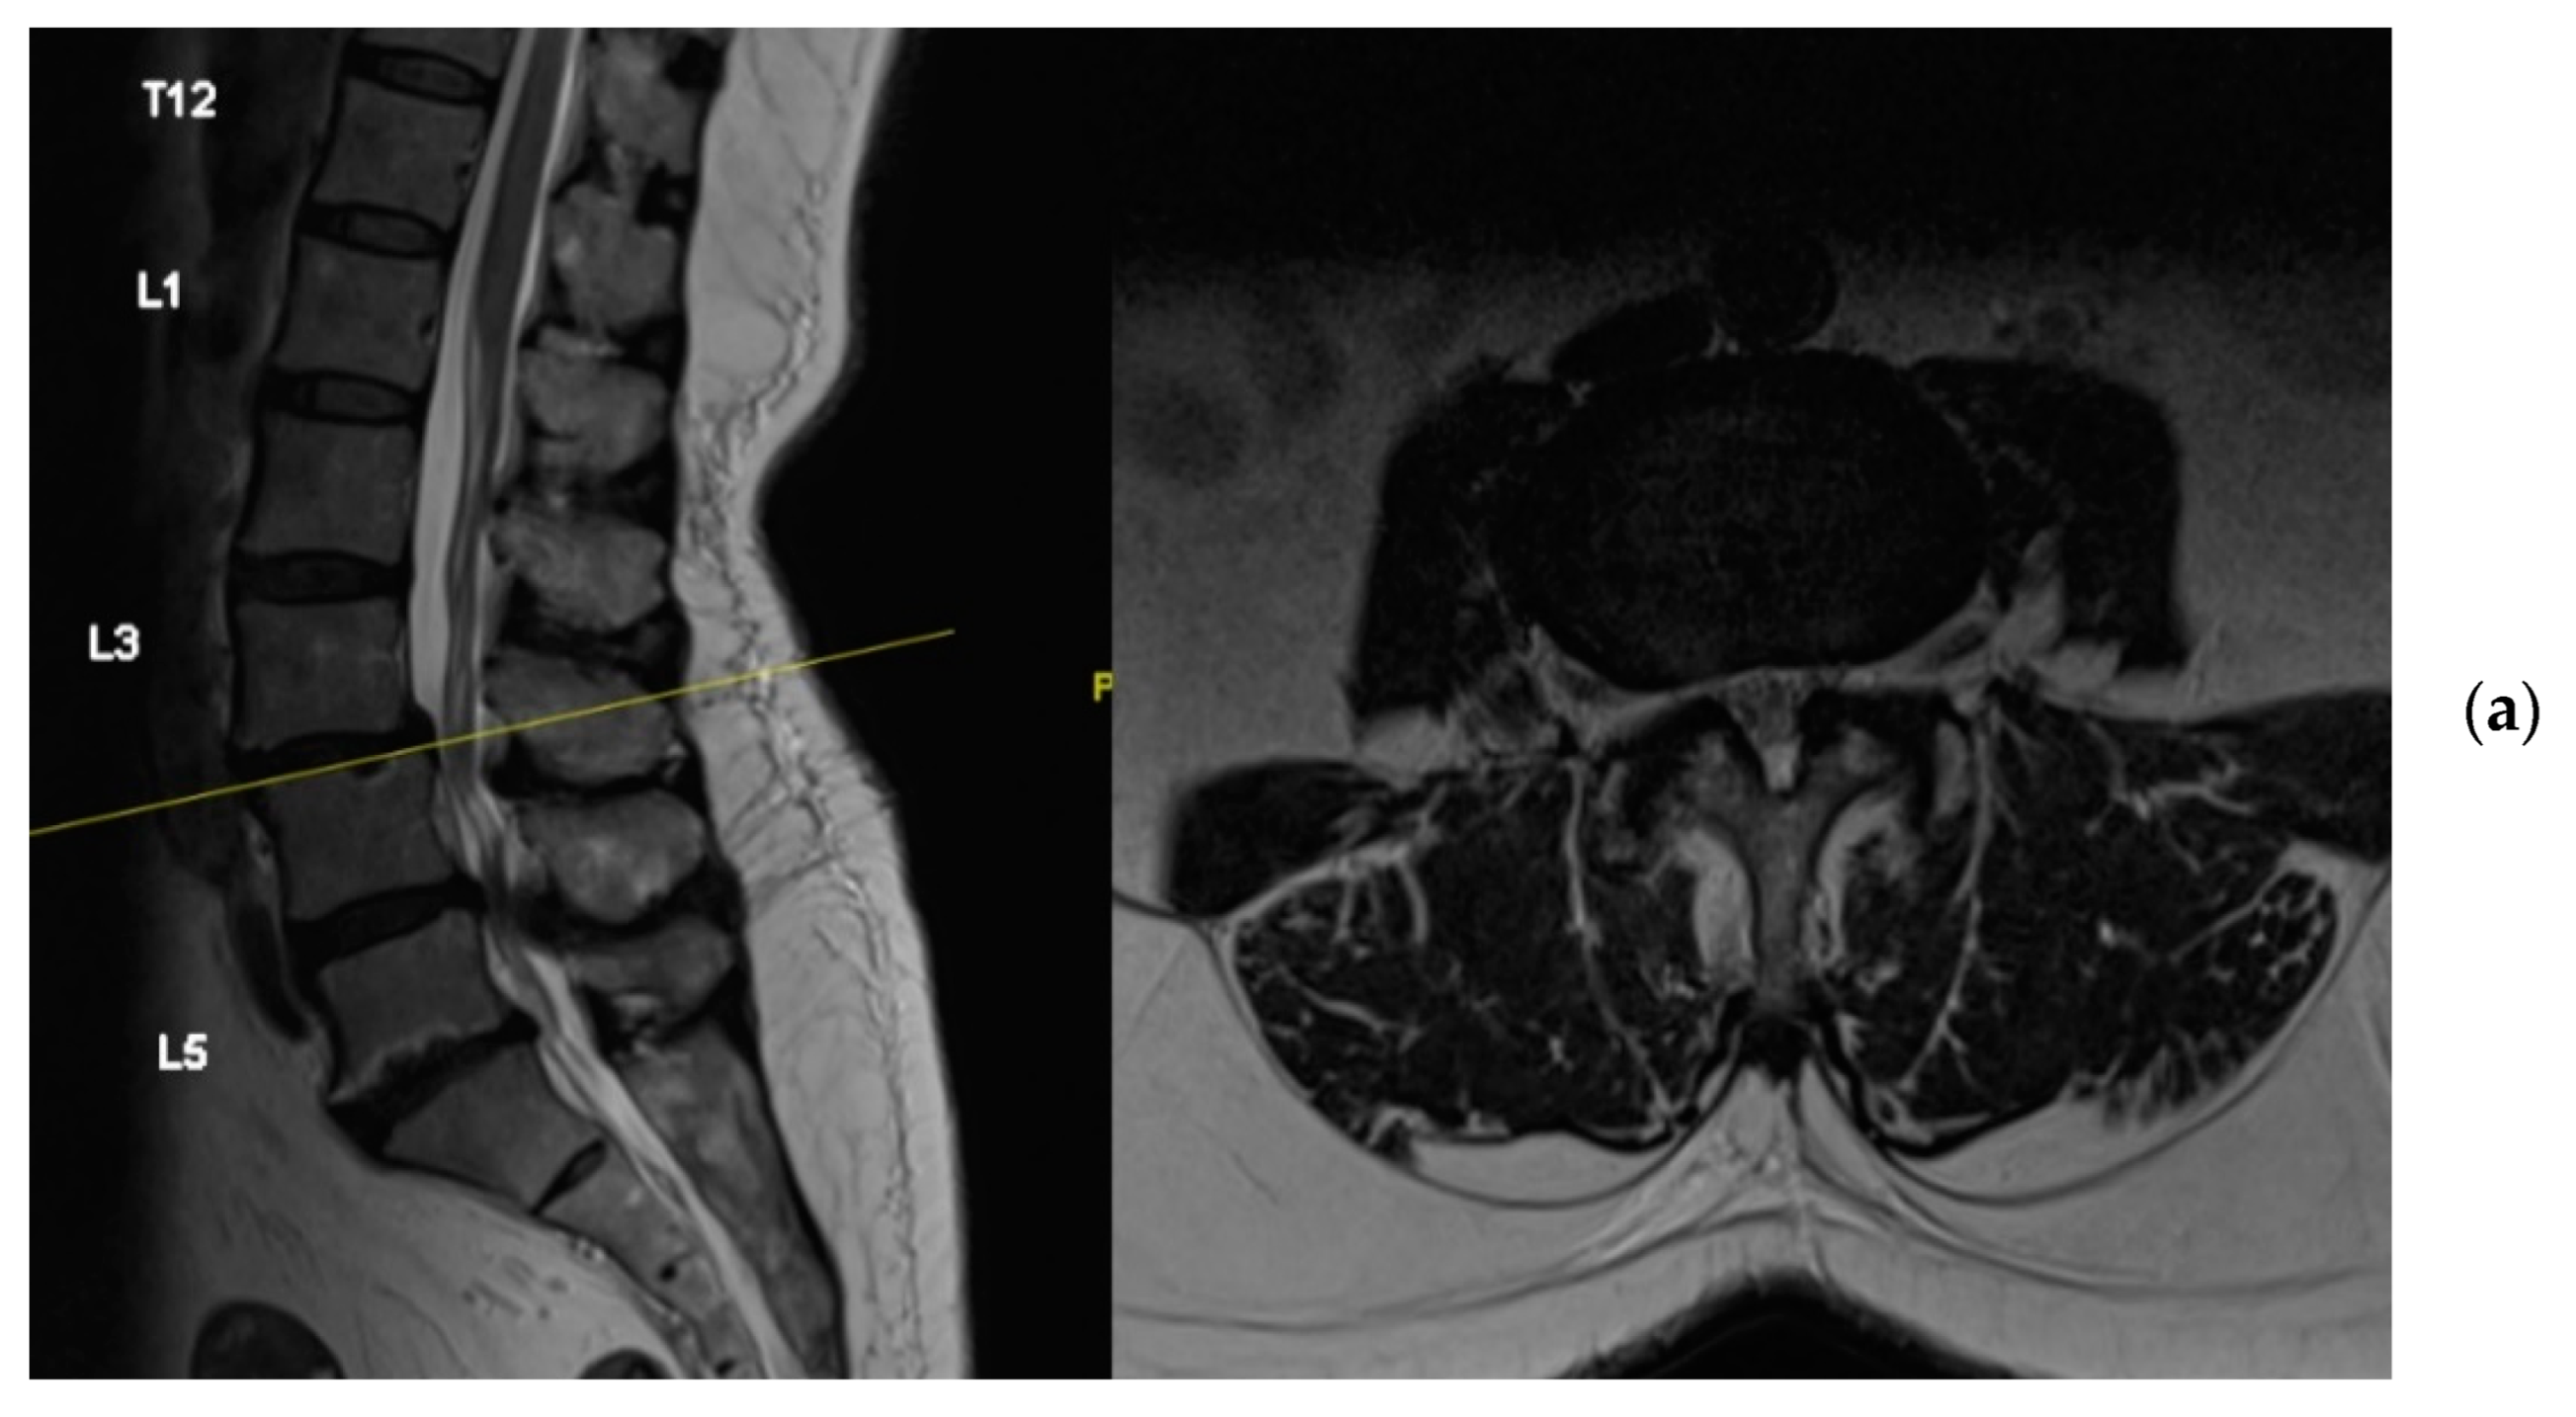

4.1. Case 1: Madam M

4.2. Case 2: Madam R

4.3. Case 3: Madam M